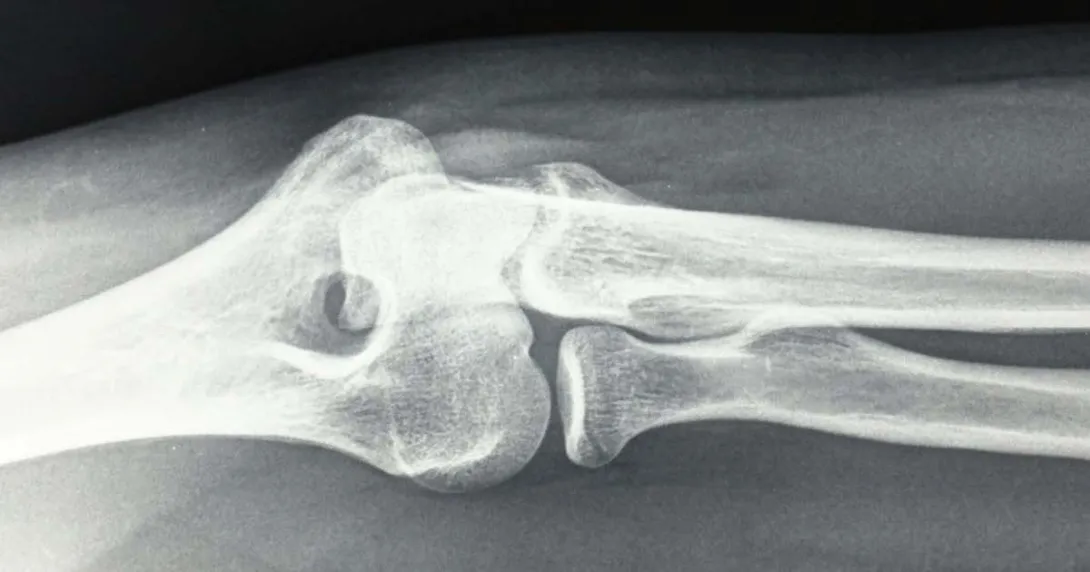

The Atlanta-based company offers an FDA 510(k)-cleared handheld X-ray system that can be used for static and serial diagnostic images of the extremities, dubbed the Micro C Medical Imaging System. The device connects directly to OXOS' cloud platform, where physicians can access images.

OXOS first received FDA clearance for its Micro C System in 2021. Last year, it acquired another FDA 510(k) clearance for the device that included its AiLARA System, an AI-automated radiation dosage engine.